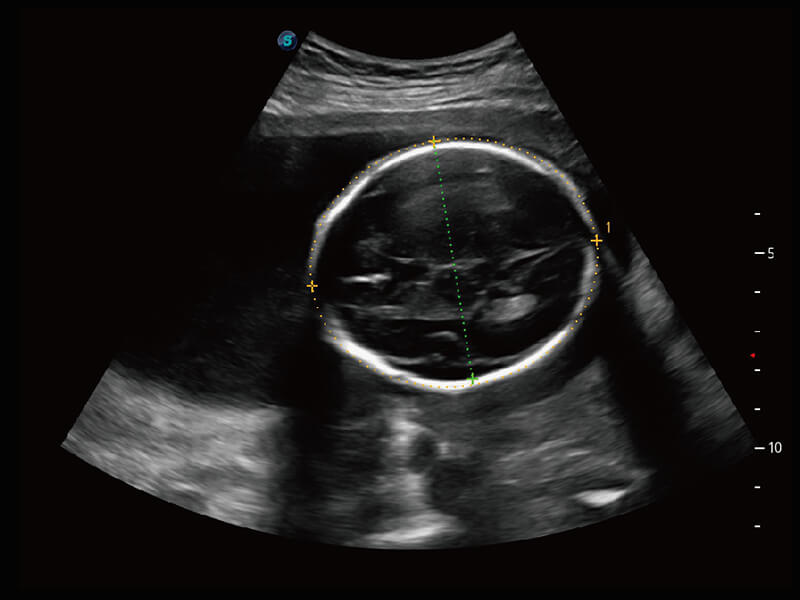

高分辨率容积成像 栩栩如生

超宽频带技术,为容积成像带来优质的二维图像基础,为您呈现丰富的结构细节,栩栩如生地展示宝宝的宫内形态以及各种组织的立体结构。

• 高分辨率容积探头( VC2-9A )